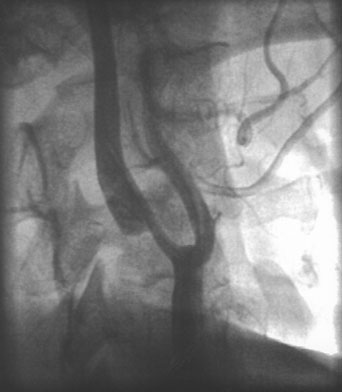

In the evaluation of extracranial large vessel disease, mainly carotid disease, ultrasound is the initial indicated study. It is commonly available, relatively inexpensive, and accurate. In addition, compared to other vascular imaging methods, it has the ability to directly image and characterize the plaque. Certain plaque characteristics may predict an increased risk of embolization. For example, the presence of an ulcer at the plaque surface may promote the formation of thrombus that can secondarily embolize, while a hypoechoic plaque, representing either intraplaque hemorrhage or a lipid-rich plaque, is associated with the potential for plaque destabilization.79,80 Carotid artery ultrasound has a sensitivity of 90% to 95% and specificity of 85% compared to catheter angiography.81 However, ultrasound may be unable to detect high-grade stenosis and mistakenly diagnose a carotid occlusion in 5% of cases. It is important to make this distinction as a patent vessel may be amenable to a revascularization procedure. Although power Doppler and echo-contrast agents may improve the odds of a correct diagnosis, for now it is standard practice to corroborate carotid occlusions with another imaging modality such as MRA, computed tomographic angiography (CTA), or conventional catheter angiography. MRA is an evolving technology comparable in accuracy to ultrasound, with the advantage of being able to image the distal carotid. In the past, there was a risk of overestimation of carotid stenosis by MRA, and beyond 70% stenosis, the absence of signal (flow gap) impeded adequate quantification of narrowing.82 Evolution in MRA technology and the use of contrast agents has improved the yield of this diagnostic method. Catheter angiography is the gold standard for carotid disease, but has inherent risks, with approximately 1% risk of stroke, although probably less in experienced centers. Figure 2 demonstrates the use of imaging technology in carotid disease.

Fig. 2. This 48-year-old diabetic man suddenly developed confusion and clumsiness of the right hand. On examination, he had inability to identify objects by touch and difficulty identifying the right from the left. A. Fluid attenuated inversion recovery (FLAIR) MRI shows a left parietal cortical infarct. Two potential embolic sources were noted: a left ventricular apical clot was seen on echocardiography from a presumed recent silent myocardial infarction, and ultrasound and subsequent angiography confirmed a significant left internal carotid stenosis. B: A 70% left internal carotid artery origin stenosis is shown on angiography. Monitoring both middle cerebral arteries with transcranial Doppler showed microembolic signals only over the left, suggesting that the carotid atherostenotic plaque was active or destabilized. C: An interruption (arrow) of the normal Doppler flow pattern of the middle cerebral artery is shown, representing a microembolic signal. The artery was stented rather than revascularized by endarterectomy because of the recent myocardial infarction. D: A patent revascularized carotid is revealed by ultrasound; note the struts of the stent.

Carotid angioplasty and stenting is a novel endovascular approach to revascularizing the carotid artery. As a technique, it is in its infancy, and catheter technology and distal protection devices to prevent periprocedural strokes are constantly evolving. To date, no randomized study has shown superiority of this technique over surgical endarterectomy in the average patient,83,84 although direct comparisons between endarterectomy, and angioplasty and stenting are currently underway.85 However, high-risk patients appear to do better with endovascular approaches.86 In the author's opinion, for now angioplasty and stenting should be reserved for symptomatic patients who cannot undergo surgery or generalized anesthesia because of cardiac or pulmonary conditions. Certain situations, such as radiation-induced arteriopathy, contralateral occlusion or high-grade stenosis, or contralateral vocal cord paralysis, are relative contraindications to endarterectomy; in their presence angioplasty and stenting is an appropriate therapeutic choice. An example of carotid stenting is shown in Figure 2.